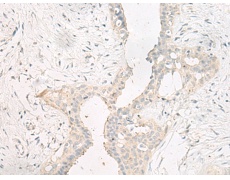

IHC positive control: |

Human cervical cancer and Human breast cancer |